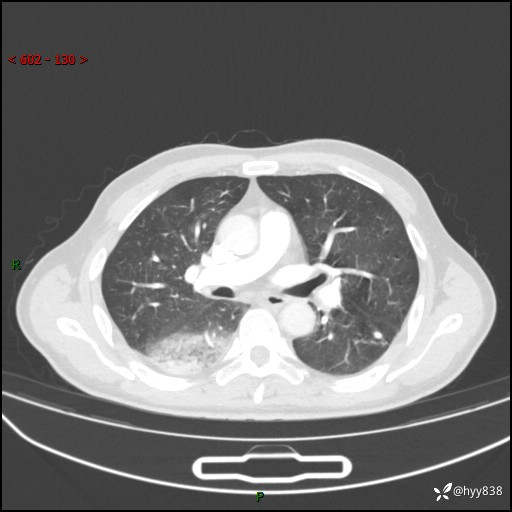

【患者信息】:63岁/男

【主诉】:发热5余天

【现病史及既往史】:患者5余天无明显诱因出现畏寒寒战发热,最高体温39.5℃,发热无明显昼夜规律,伴全身乏力、头晕,无头痛、无咳嗽咳痰、无胸痛咯血、无气短、无腹痛腹泻、无尿频尿急尿痛等不适,于当地市第五人民医院就诊,予以抗感染等治疗(具体不详)后发热无明显好转,1天前查胸部CT提示右下肺感染,为求进一步诊治,门诊以“社区获得性肺炎”收治入院; 起病以来,患者精神、食欲一般,睡眠可,大小便正常,体力体重较前无明显变化。

【检查】:胸部CT增强